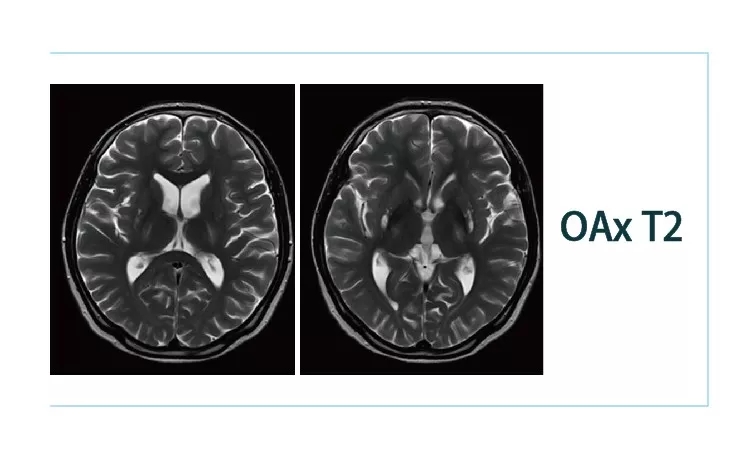

1544579634898245.jpg1544579646797662.jpg